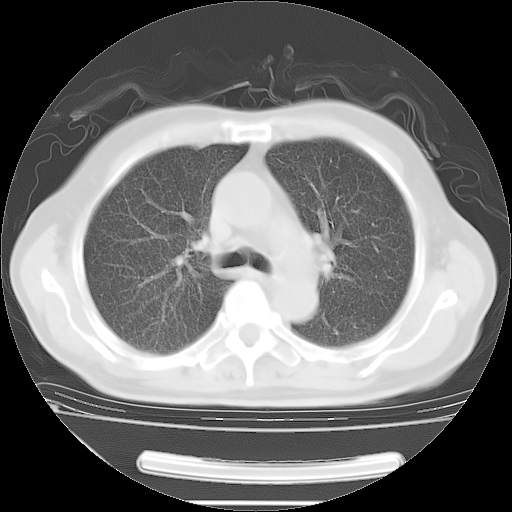

胸腹部CT,诊断意见:左上肺叶钙化灶、左侧胸膜局限性增厚并钙化、胆囊炎。描述部分肺组织呈磨玻璃样改变。